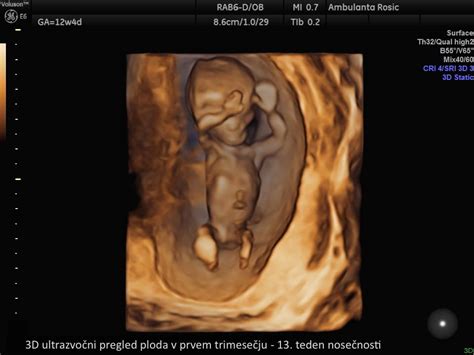

Na koncu prvega trimesečja, v 13. tednu, plod meri 7,4 cm in tehta do 23 gramov. Glavica še vedno predstavlja polovico njegove dolžine, okončine pa hitro rastejo. Jutranje slabosti se pogosto umirijo, lahko pa se pojavi zgaga.